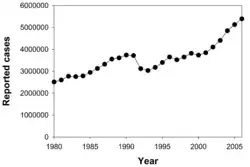

Předpokládá se, že třetina světové populace je infikována bakterií M. tuberculosis[1][7] a zhruba každou sekundu je infikován nový člověk.[1] Procento celosvětové populace, které každý rok onemocní tuberkulózou, zůstává stejné nebo klesá, ale v důsledku růstu populace se počet nakažených zvyšuje.[1] V roce 2007 bylo odhadováno na 13,7 milionů chronických aktivních případů, 9,3 milionů nových případů a 1,8 milionů úmrtí, a to většinou v rozvojových zemích.[8] Ve světě není tuberkulóza rozšířena rovnoměrně – v mnoha asijských a afrických zemích je jí nakaženo až 80 % obyvatel, kdežto ve Spojených státech jen 5–10 %.[3] V Česku bylo v roce 2023 hlášeno 459 onemocnění tuberkulózou, tj. 4,2 případu na 100 000 obyvatel,[9] v roce 2009 to bylo 710 případů, tj. 6,8 na 100 tisíc obyvatel.[10]

Bakterií M. tuberculosis je nakažena zhruba třetina světové populace a zhruba každou sekundu je infikován nový člověk.[1] Ne všechny tyto nákazy ale způsobují tuberkulózu a některé jsou asymptomatické.[63] Předpokládá se, že v roce 2007 bylo na světě zhruba 13,7 milionů lidí s aktivní formou tuberkulózy, z toho 9,3 milionů bylo nových případů. Ve stejném roce na tuberkulózu zemřelo 1,8 milionu lidí. Roční incidence se pohybovala mezi 363 případy na 100 000 lidí v Africe a 32 případy na 100 000 lidí v Americe.[8] Tuberkulóza způsobuje z infekčních onemocnění nejvíce úmrtí žen v reproduktivním věku a je jednou z hlavních příčin úmrtí u lidí s HIV/AIDS.[64]

Zvyšování počtu nákaz virem HIV a zanedbávání programů na kontrolu tuberkulózy vedly k nové vlně tohoto onemocnění.[65] Přispěl k tomu i nástup rezistentních typů tuberkulózy, kdy mezi lety 2000 a 2004 bylo 20 % případů rezistentních proti prvořadým antibiotikům a 2 % i proti druhořadým.[66] Rychlost výskytu nových onemocnění tuberkulózou se velmi liší, a to i u sousedních států, nejspíše kvůli rozdílům ve zdravotních systémech.[67]

V roce 2007 bylo státem s největší incidencí Svazijsko s 1200 případy na 100 000 lidí. Indie měla nejvíce nově nahlášených případů – 2 miliony.[8] Ve vyspělých zemích je tuberkulóza méně častá. Ve Spojeném království v roce 2007 činil národní průměr 15 nových případů na 100 000 lidí a největší míra incidence v západní Evropě byla 30/100 000 v Portugalsku a Španělsku. V Číně to pak bylo 98/100 000, v Brazílii 48/100 000 a ve Spojených státech 4/100 000.[61] V Kanadě se tuberkulóza vyskytuje v některých venkovských oblastech.[68] V Česku v roce 2007 činila incidence 9/100 000 s celkovým počtem 893 nakažených.

V 10. letech 21. století byl zaznamenán v Evropě nárůst počtu případů tuberkulózy, způsobený i migrací množství obyvatel ze zemí s velkým výskytem onemocnění. Ve Francii, Spojeném království, Německu a Španělsku bylo v roce 2014 zaznamenáno 75 % všech případů tuberkulózy právě u cizinců. I proto byly doporučeny u migrantů screeningové programy.[69]